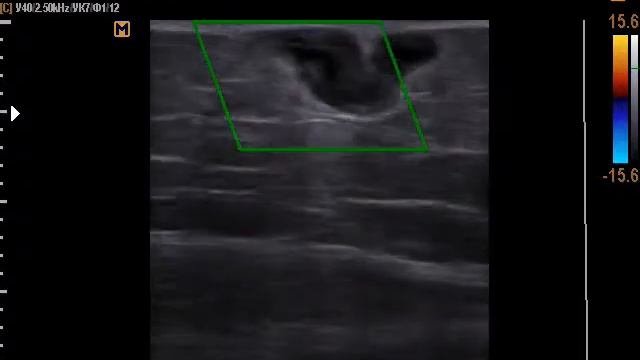

Сколиоз 3 степени Результат на 100 день - видео

Пациентка М.Сколиоз 3-степени.Результат на 100 день.Продолжение следует до полного выпрямления.Учтитерезультат полученн в домашних условиях.,